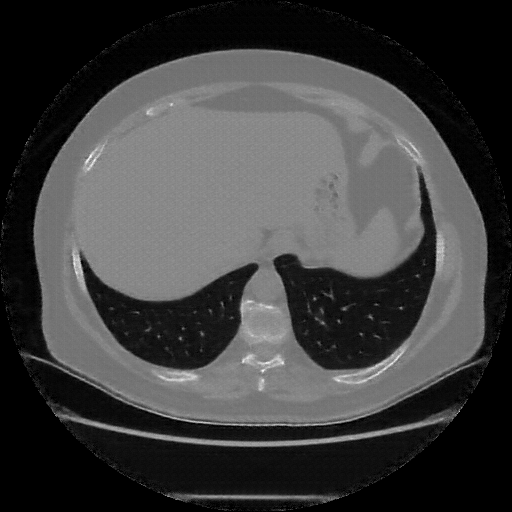

Reconstructed NATIVE CT scan (cycle consistency)

Full window (WL 1023.5, WW 4095 β†’ Low βˆ’1024, High +3071)

Actual HU range: [-1024.0, 993.2]